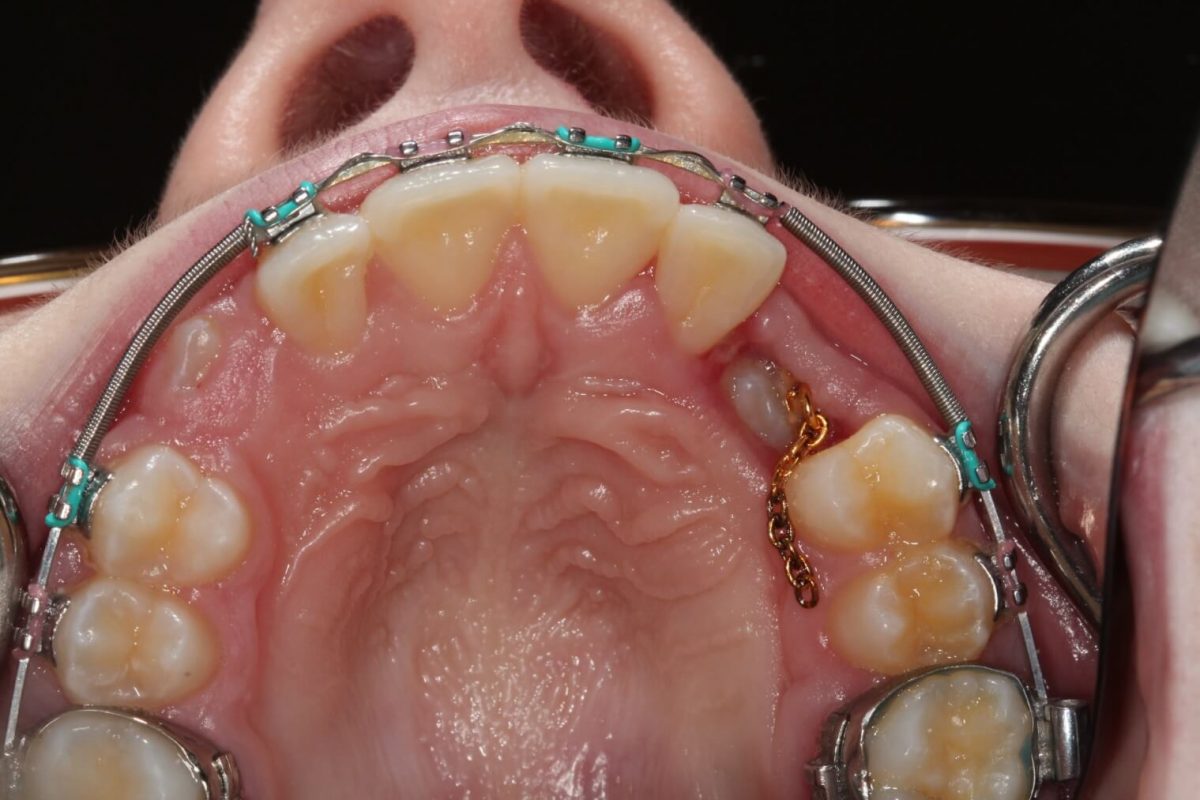

3 Surgical exposure of canine and bonding of orthodontic button with a... Download Scientific Orthodontic Canine Exposure — corrective orthodontic therapy was associated to a rapid maxillary expansion and to the use of a high pull. — when starting comprehensive orthodontic treatment, it is important to first distalize the canine away from the incisor root before pulling in out into. — this systematic review compares the outcomes of open and closed surgical exposure of. Orthodontic Canine Exposure.

An Open Exposure "Window" for an orthodontic forced eruption of... Download Scientific Diagram Orthodontic Canine Exposure bringing the impacted canine into a normal position is important for functional occlusion and the final esthetics of the orthodontic. — this systematic review compares the outcomes of open and closed surgical exposure of permanent impacted. — orthodontic treatment of palatally displaced canines may be extremely challenging, often with. impaction of maxillary and mandibular canines is. Orthodontic Canine Exposure.